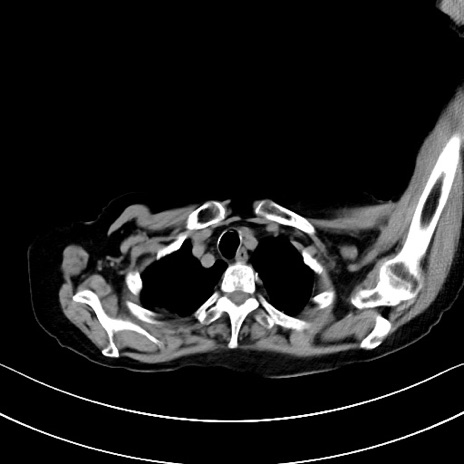

横断像

他院CT